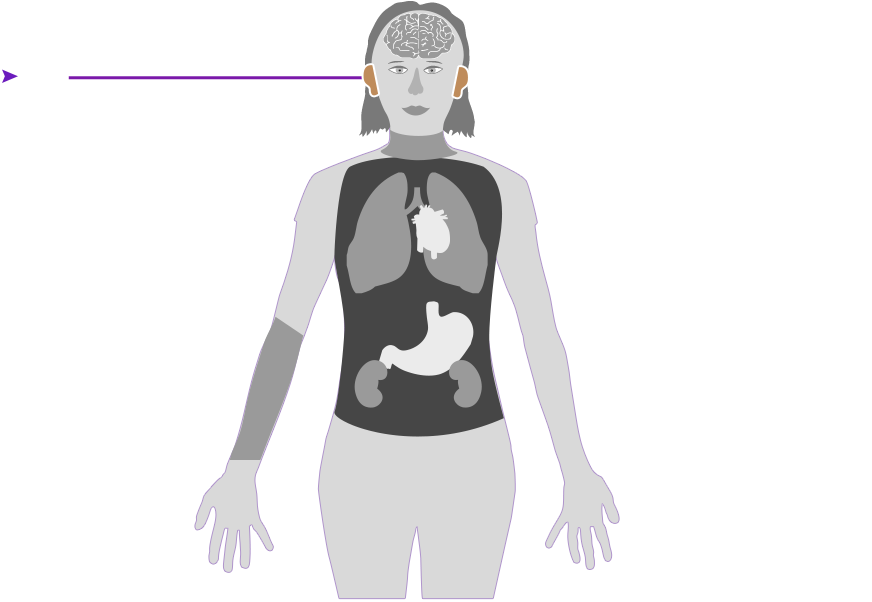

Check out how mercury can affect the human body. Click on the different parts of the body to see what can happen when people are poisoned by mercury. How serious these health effects are may vary depending on how much mercury gets into your body — and how long you breathe it in.

Health effect caused by breathing in high levels of mercury vapors (fumes) over a short period of time

Health effect caused by breathing in high levels of mercury vapors (fumes) over a short period of time  Health effect caused by breathing in lower levels of mercury vapors over a long period of time